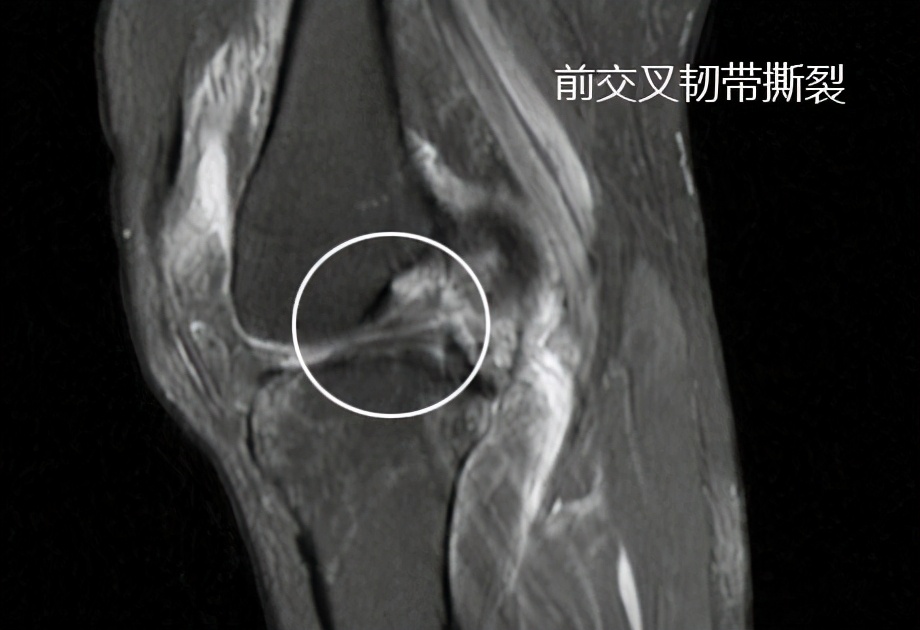

另外老人的前交叉韧带真的像预估的一样,发生了明显的撕裂,我们可以看到在核磁影像上有经典的对吻伤,也就是说韧带撕裂的时候,股骨远端与胫骨平台发生了撞击,造成了骨头的挫伤,在骨头内可以看到明显的水肿信号。

而且,前交叉韧带也撕裂了,半月板在核磁影像上看起来还是比较不错的。